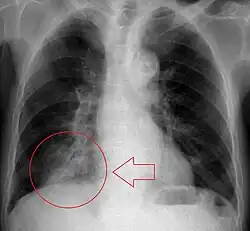

Chest X-rays can be useful in the diagnosis of aspiration pneumonia but may be negative early in the course.[12] Chest CT Scan can identify the presence of a pneumonia as well, and can also assist in characterizing abscesses, foreign objects, or pleural disease.